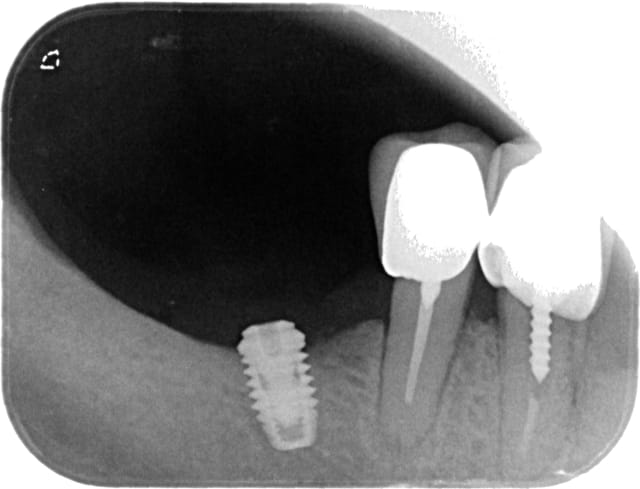

j'ai posé cet implant il y a 3 mois chez ce patient qui ne souhaitait pas de greffe. L'intervention et les suites opératoires ont été classiques. Aujourd'hui mise en place de la vis de cica et radio.

implant diametre 4.2, largeur de crete 6mm. Tu penses que c'est la le prb?

sinon, je pense que l'implant n'est pas assez enfoui, d’où colonisation et periimplantite...

à la mandibule il faut 1mm mini en vestibulaire et en lingual et donc là tu ne les as pas...

pour peu que ton implant ait été compressif en crestal et là c'est la mort des cellules osseuses qui ne sont plus assez "nourries", et on arrive à la situation présente...

au stade où tu es, perso c'est dépose, ROG "piquet de tente", et repose à 4/5 mois dans un axe plus favorable...çà serait mieux vu que tu n'as visiblement en plus pas beaucoup de hauteur...